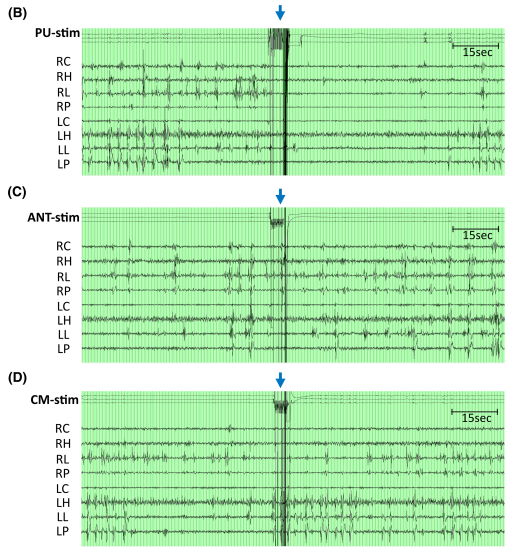

(2)刺激后IED變化

刺激后30秒IED(發(fā)作間期癲癇樣放電)減少率顯著高于60秒(30秒vs.60秒:199/368 vs.158/368,p=0.003)??傮w而言,三個(gè)丘腦核團(tuán)刺激后雙側(cè)后象限區(qū)域的IED減少最為顯著,其中枕核刺激效果最佳。50Hz與100Hz刺激的IED減少率顯著高于1Hz刺激?;颊呶磮?bào)告任何刺激相關(guān)副作用(≤2mA,40μC/cm2)。